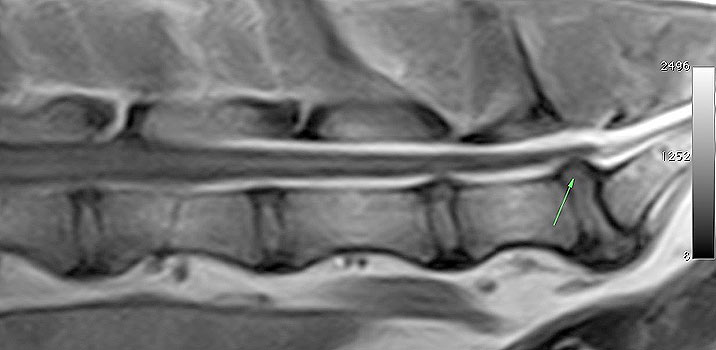

Een MRI-scan is een langdurig onderzoek waarbij het dier volledig stil moet liggen. Anesthesie is dan ook onontbeerlijk.